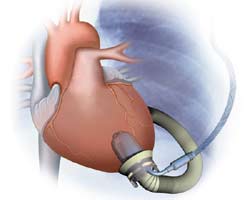

Off-Pump Insertion of the Jarvik 2000 Left Ventricular Assist Device

The Jarvik 2000 is an axial-flow pump involved in a FDA-approved phase II clinical pivotal trial in Status I patients as a bridge to transplantation (Figure 1). Although well over 100 implants have been performed in the United States and Europe during the feasibility trials, these devices have typically been inserted either by sternotomy or thoracotomy with the use of CPB. Our current approach is 2-pronged: in patients who are hemodynamically unstable leading to LVAD insertion, we have opted for placing these patients on CPB; for those who are hemodynamically stable, we perform the procedure off-CPB. To date, we have implanted this LVAD in 11 patients (2 who required CPB secondary to cardiovascular collapse). All patients were NYHA class IV on multiple inotropic drugs with impaired end-organ function. Implants without cardiopulmonary bypass had decreased transfusion requirements, fewer days on the ventilator, shorter ICU stays, and fewer adverse events including ventricular and supraventricular arrhythmias, need for dialysis, and bacterial and fungal infections [5]. Because of its size and construction of inflow and sewing ring, it is simple to place intrathoracically and is particularly suited for patients with previous heart operations in order to avoid redo-sternotomy.